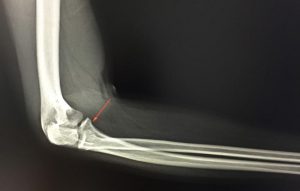

Τύποι, Συμπτώματα και Θεραπεία Ο αγκώνας είναι μια σύνθετη άρθρωση που σχηματίζεται από το βραχιόνιο, την κεφαλή της κερκίδας και...

Αρθρίτιδα αγκώνα – Συμπτώματα, αίτια και θεραπείες Η αρθρίτιδα του αγκώνα είναι λιγότερο συχνή σε σχέση με άλλες αρθρώσεις (π.χ....